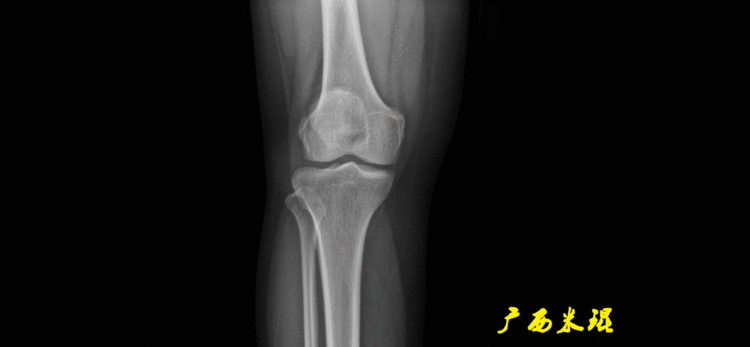

无论如何,拍摄出来的下肢全长片必须包含髋关节中心、膝关节中心及踝关节中心,否则对临床是无用的。有了一张下肢的全长照片,我们需要确定下肢关节的中心点,通过中心点画出下肢的各种轴线,然后利用轴线与关节线的相交得出各种所需要的角度。

(2)膝关节中心膝关节中心点常用的有5个不同的定位方法,分别是股骨髁中点、股骨髁间窝顶点、膝关节间隙水平软组织中点、胫骨髁间嵴中点和胫骨平台中点,我们可以根据具体情况来选用。

(2)股骨远端关节线正位为股骨内外侧髁最低点之间的连线。髌骨下极在此线之上,距离大于20mm可考虑为高位髌骨。

(3)胫骨近端关节线正位为胫骨内外侧平台最低点之间的连线。